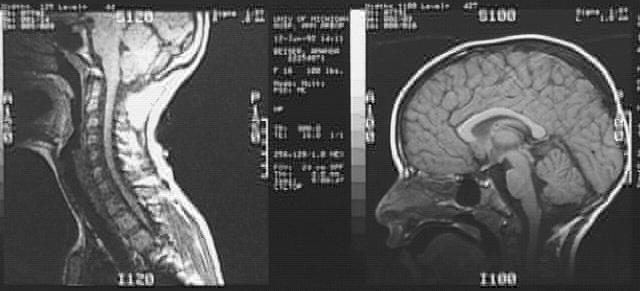

Head & Neck:Head MRI 1 of 3: